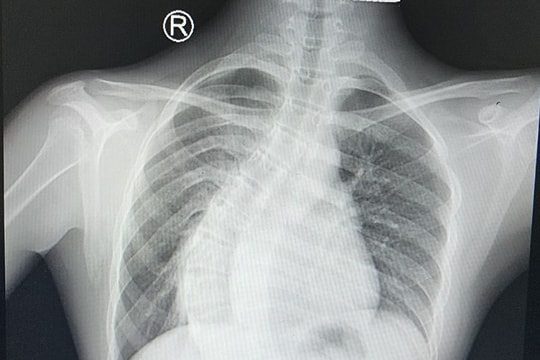

Bệnh viện Đại học Y khoa Phan Châu Trinh điều trị thành công bệnh nhi bị sởi biến chứng viêm phổi

09/03/2025 15:33

(QNO) - Bệnh viện Đại học Y khoa Phan Châu Trinh (phường Điện Ngọc, TX.Điện Bàn) vừa tiếp nhận và điều trị thành công một trường hợp bệnh nhi 11 tuổi mắc sởi biến chứng viêm phổi nặng.